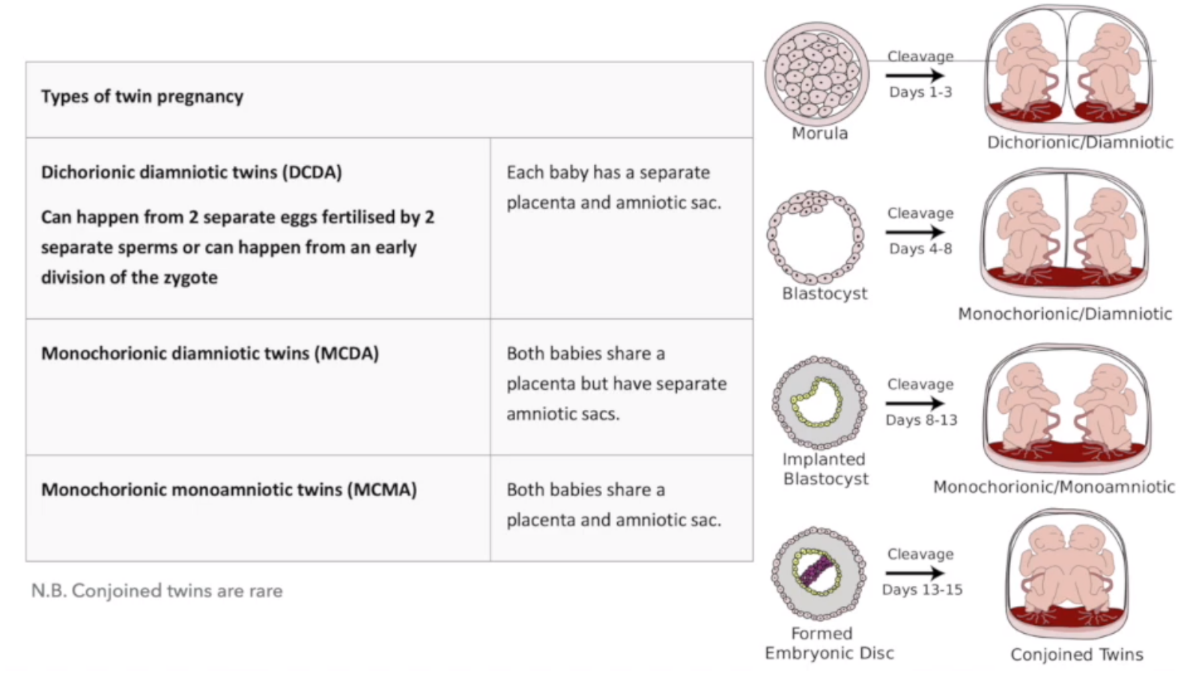

What are the different types of twin pregnancies?

What does DCDA stand for?

Dichorionic diamniotic twins

What does MCDA stand for?

Monochorionic diamiotic twins

What does MCMA stand for?

Monochorionic monoamniotic twins